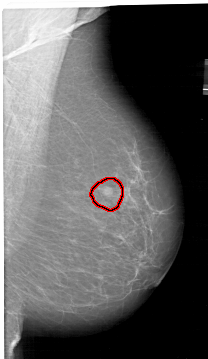

A_1409_1.RIGHT_CC

LEFT_CC LINES 6871 PIXELS_PER_LINE 3946 BITS_PER_PIXEL 12 RESOLUTION 43.5 NON_OVERLAY

FILE: A_1409_1.RIGHT_MLO.OVERLAY

TOTAL_ABNORMALITIES 1

ABNORMALITY 1

LESION_TYPE MASS SHAPE ROUND MARGINS ILL_DEFINED

ASSESSMENT 4

SUBTLETY 4

PATHOLOGY BENIGN

TOTAL_OUTLINES 1

BOUNDARY